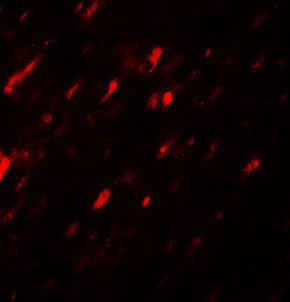

Immunofluorescence of ANGPTL3 in rat heart tissue with ANGPTL3 antibody at 20 ug/mL. |